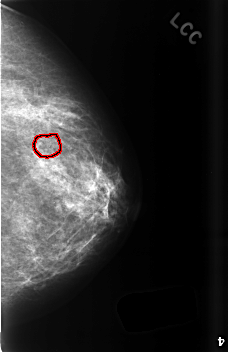

C_0503_1.LEFT_CC

LEFT_CC LINES 4576 PIXELS_PER_LINE 2952 BITS_PER_PIXEL 12 RESOLUTION 50 OVERLAY

FILE: C_0503_1.LEFT_CC.OVERLAY

TOTAL_ABNORMALITIES 1

ABNORMALITY 1

LESION_TYPE CALCIFICATION TYPE AMORPHOUS DISTRIBUTION CLUSTERED

ASSESSMENT 3

SUBTLETY 2

PATHOLOGY BENIGN

TOTAL_OUTLINES 1

BOUNDARY